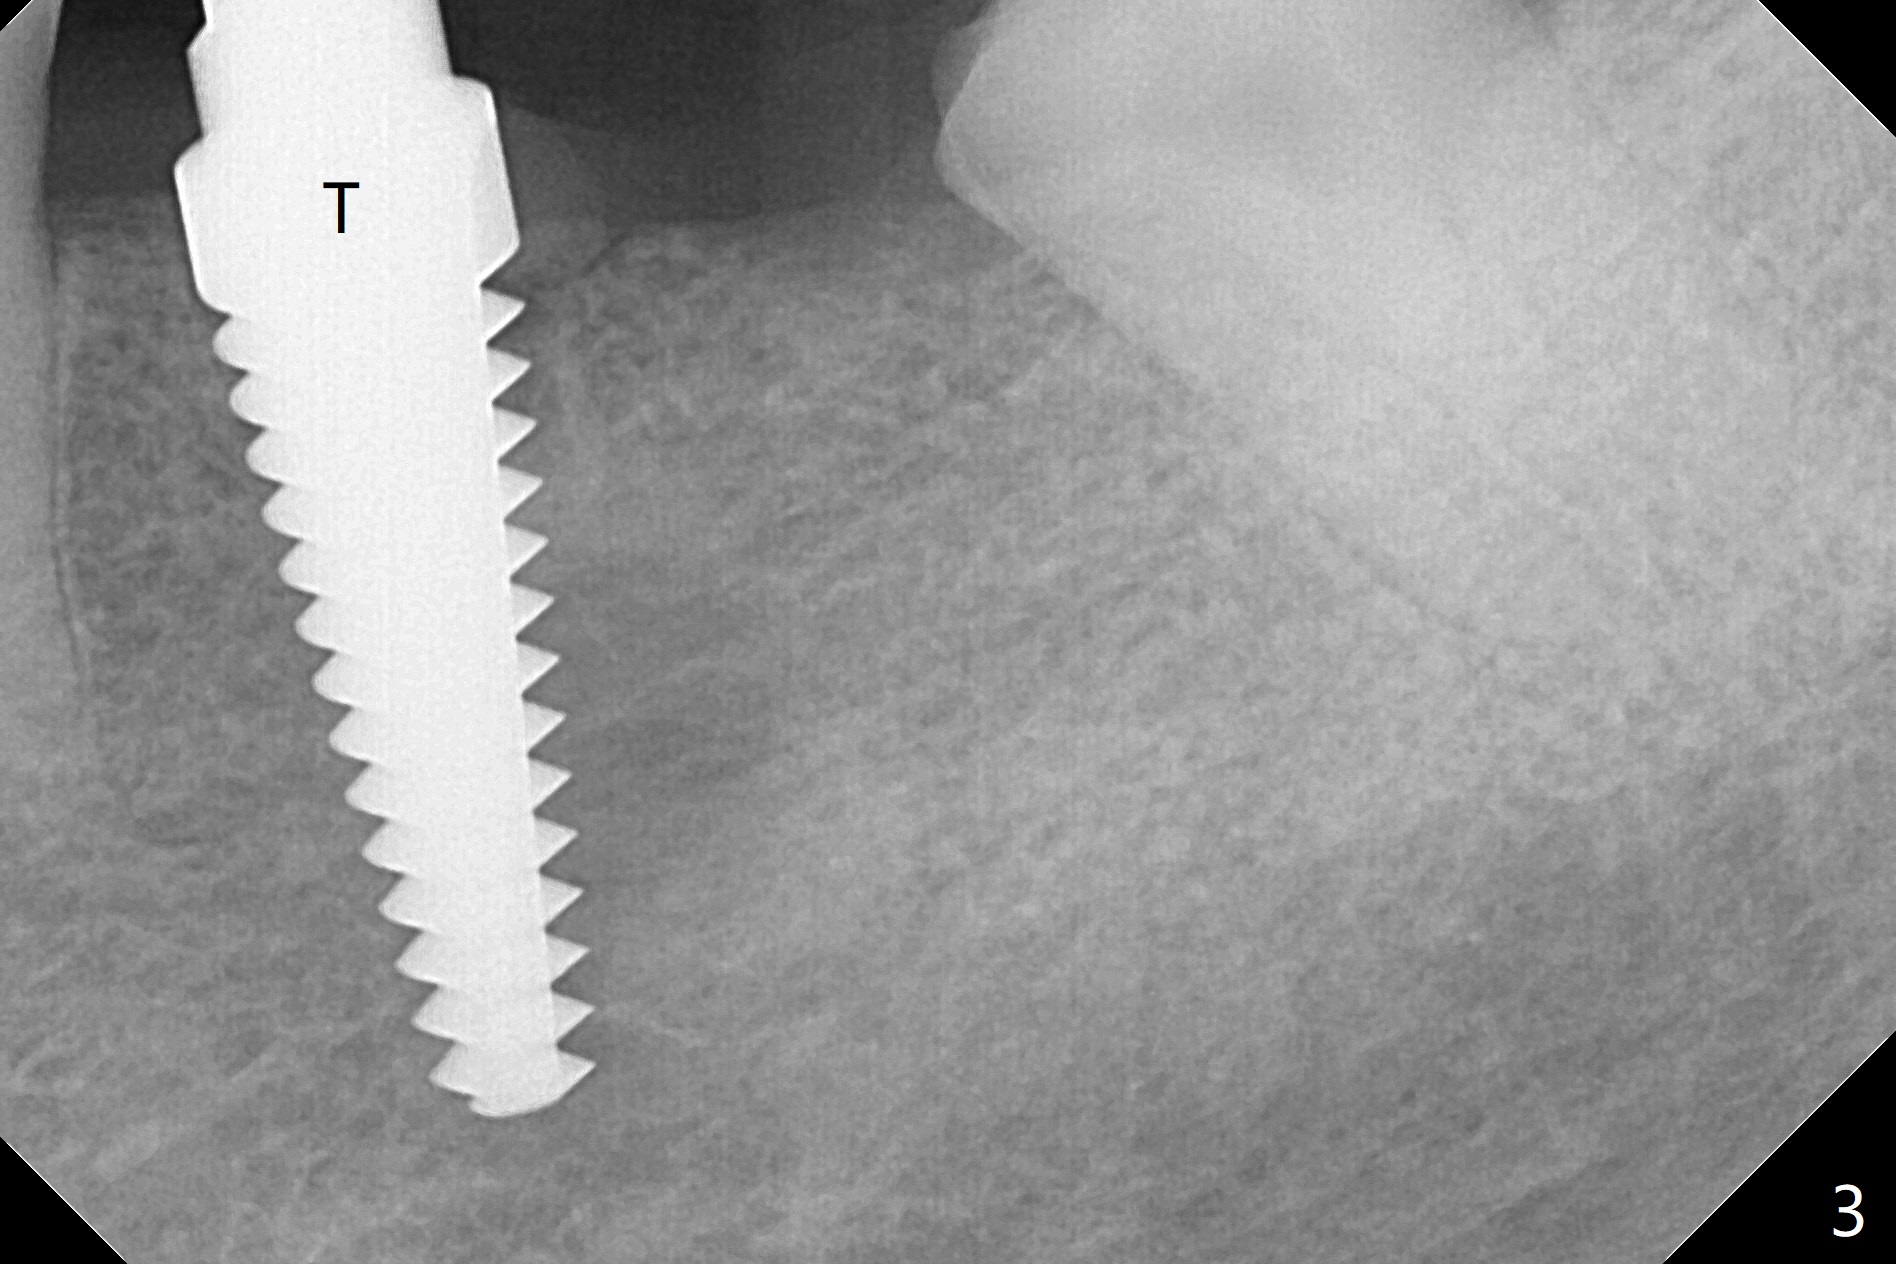

When the tooth #20 is extracted, the buccal and lingual plates are intact, but the apical lesion is deep. A PA is taken (Fig.1). Osteotomy will be established either along the long axis of the original socket (Fig.2 a line) or in the mesial slope (b line). Either osteotomy may damage the Mental Loop (red dashed line). To reduce the complication, osteotomy is being made by inserting 3.8 to 6 mm taps. In fact the 6 mm tap achieves stability (Fig.3,4), but it invades the buccal gap. When the tap is removed, the bottom of the socket is sensitive to probing with oozing from the socket. To reduce further compromise of the buccal space, Lindamann bur is used to remove the bone from the lingual and mesial plate, followed by placing a 6x17 mm implant with >50 Ncm (Fig.5). In fact the implant is placed shallower than the tap. When a 4x17 mm implant is placed at #19, there seems to be clearance from the Inferior Alveolar Canal (Fig.6). Postop there is no paresthesia. The buccal gap is <1 mm, which is filled with Vanilla Graft. After recementing the retainer (crown, C in Fig.7) at #18, periodontal dressing is applied to the sites of #19 and 20. Impression is taken 4 months postop with that of #15.